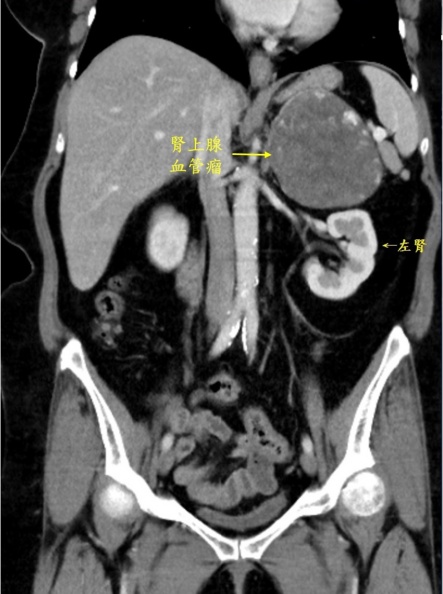

蔡女士有輕微高血壓及糖尿病,但是多年來持續服藥,控制很良好,覺得自己還挺健康的,身體都沒什麼大問題。因此日前她發現上腹部悶悶脹脹的,看很多醫療新聞,都說上腹部悶脹感是不太好的症狀,就趕快就醫,沒想到醫師檢查,在超音波檢查下,還真的發現她的左側腎臟上緣有一顆10公分的大腫瘤。

因為腎上腺腫瘤問題大,醫療團隊擔心有惡性風險,趕快將她轉介給泌尿科游智欽醫師,醫師以腹腔鏡手術,將蔡女士如芒果大的腫瘤,連同腎上腺一同摘除。進一步化驗,發現蔡女士的腫瘤是全球只有60個病例報告、極罕見的良性腎上腺血管瘤。所幸此腫瘤為良性,蔡女士在術後3天便平安出院,恢復也很順利,日後只需定期回診追蹤即可。

雖然蔡女士的是血管增生引起的血管瘤,是良性的沒有轉移問題。但是腫瘤大到10公分,因為其血管豐富,若不慎撞到或是跌倒,可能造成血管瘤破裂,導致嚴重內出血,危及生命。因此游智欽在會診新陳代謝科抽血、驗尿,確定蔡女士的醛固酮、腎上腺皮質醇與腎上腺素等數值都正常、排除功能性特殊腫瘤的風險,安排電腦斷層,確定腫瘤沒有侵犯周圍器官進行手術。